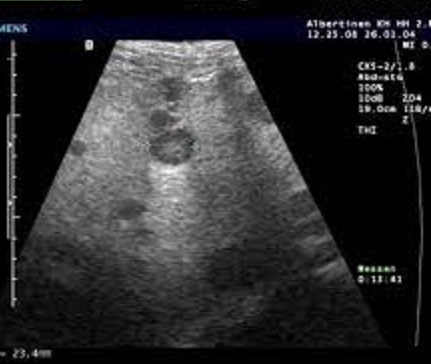

Image echographique du metastase hepatique :

Aspect est variable , souvent multiple a des nodules hypo ,

isoechogene avec contour de hypoechogene , parfoie est

hyperechogene

Image echographique de

metastase du foie : Aspect lesionaire est multiple

en nodulaire iso echogen avec contour

hypoechogen ( Bull's eye sign) |

Signe de "Bull

eye sign" des metastases du foie . Image

echographique du foie |